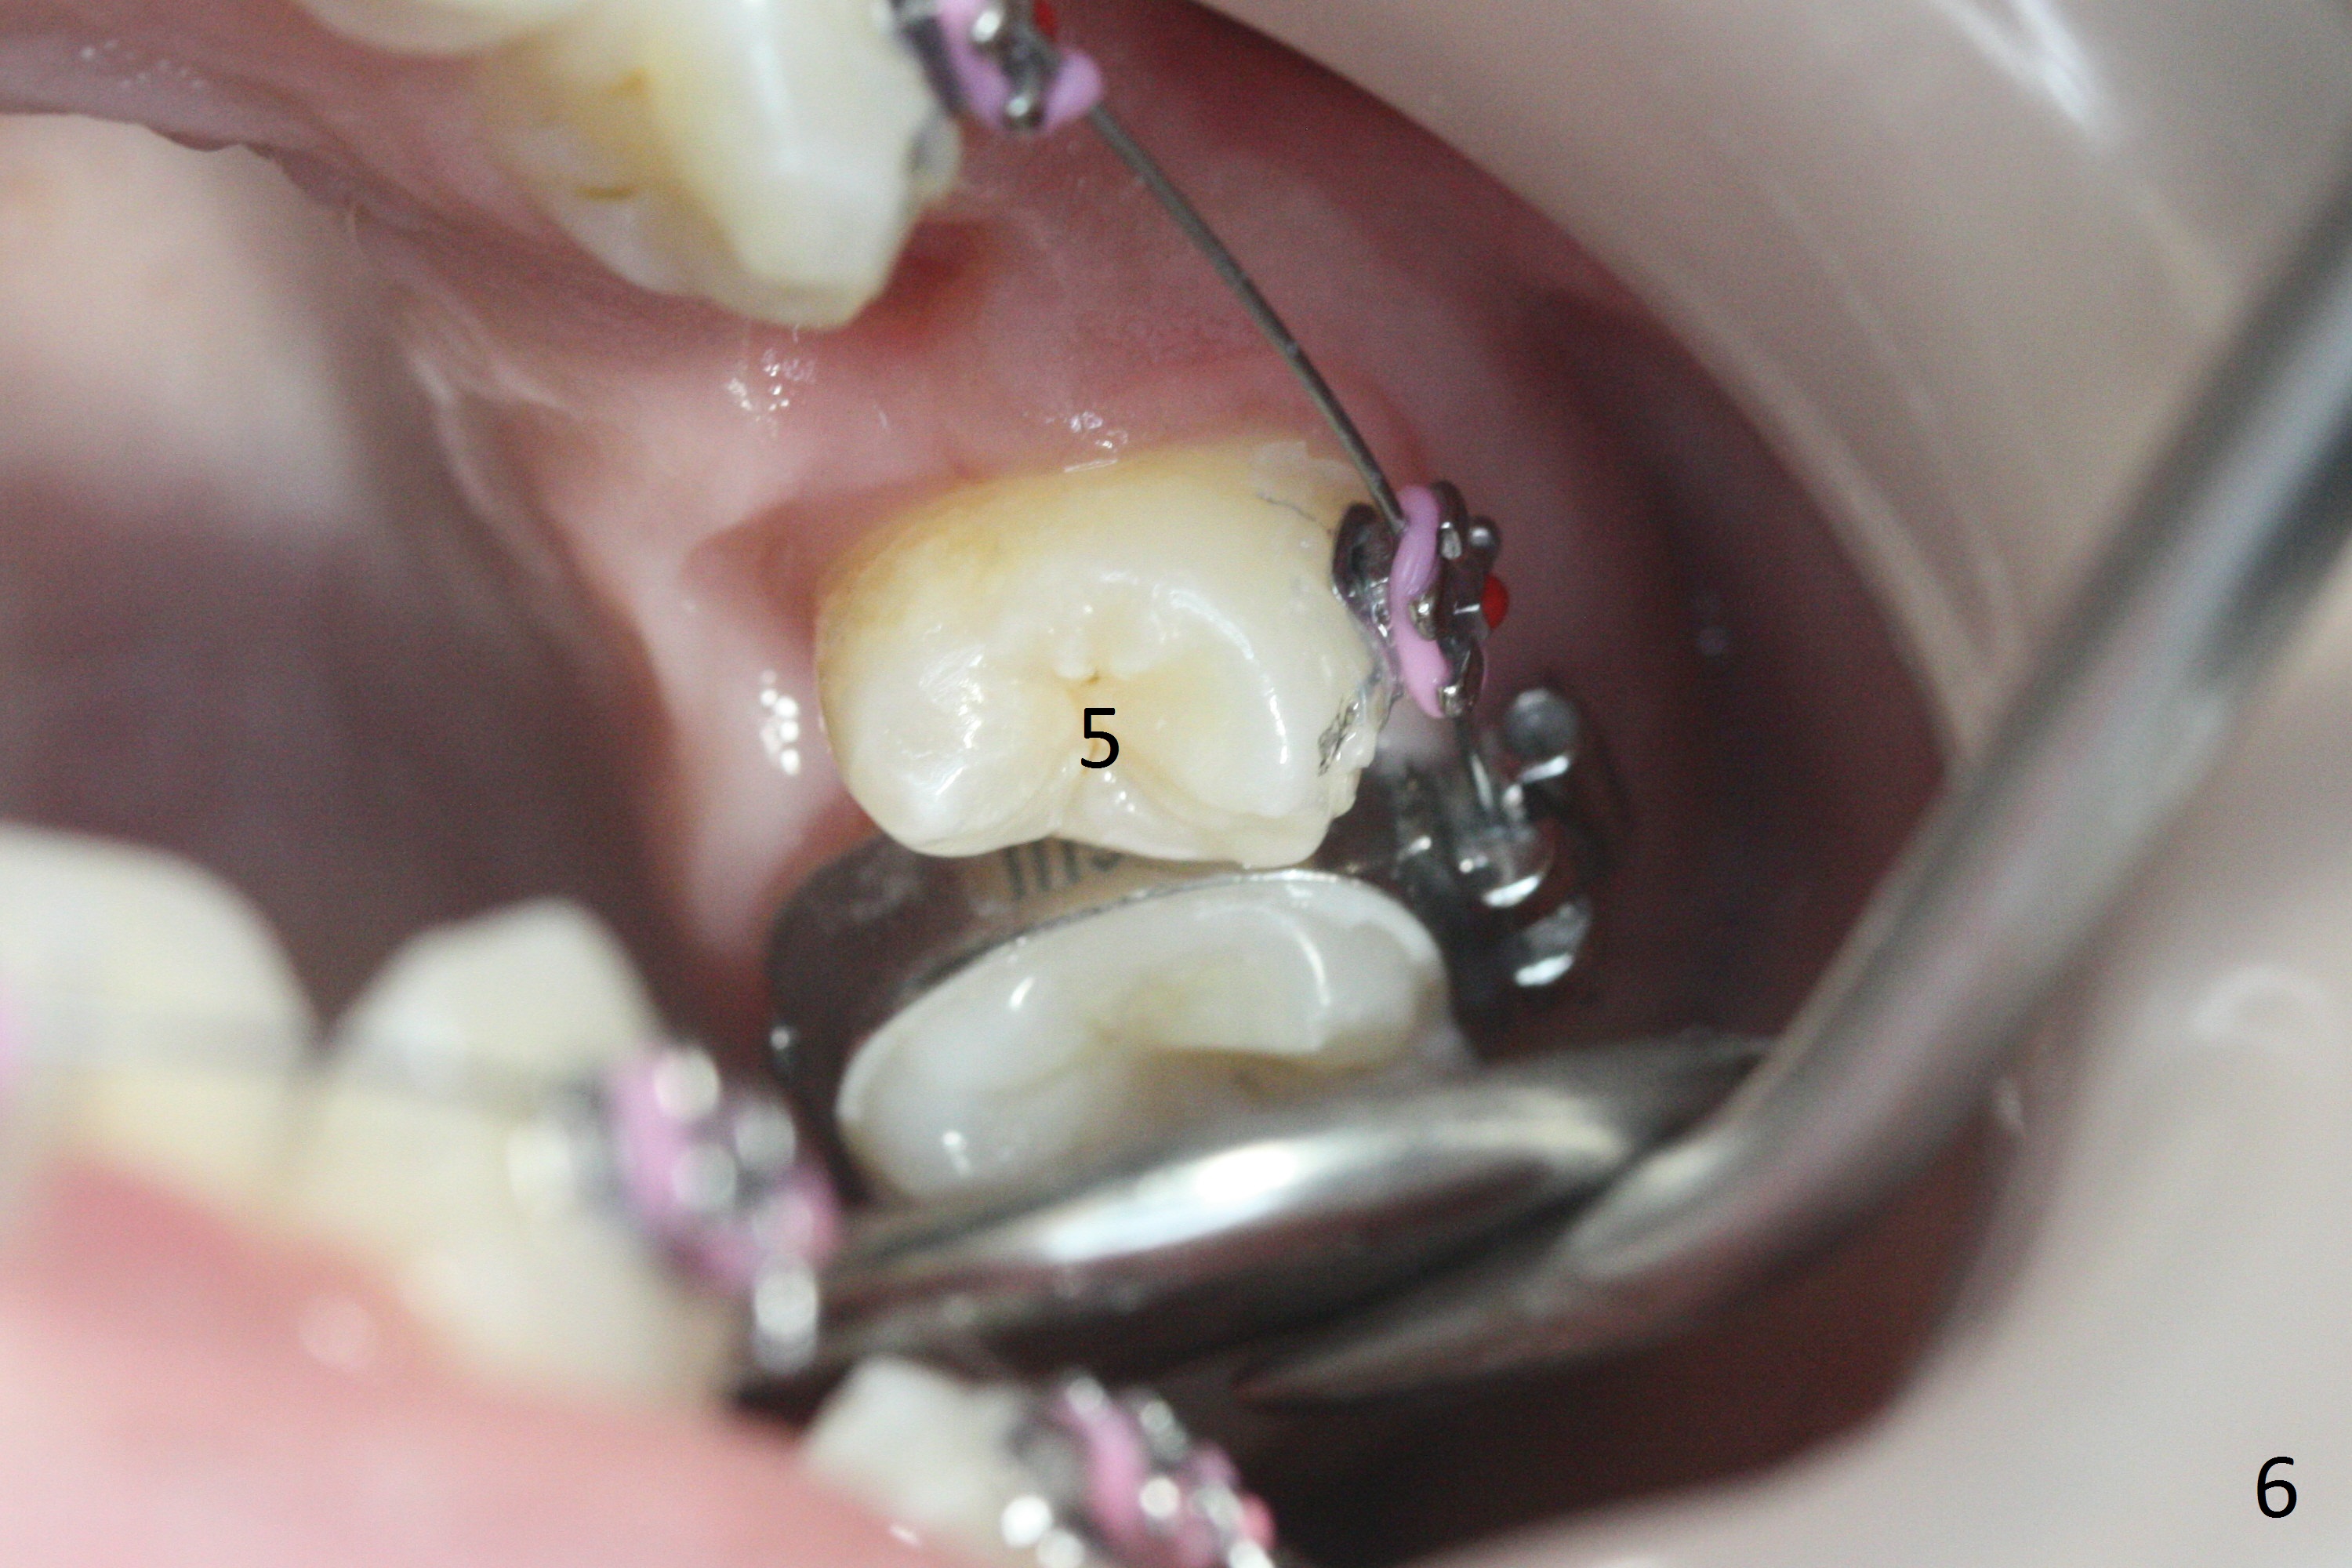

In fact there is enough space for banding at LL6 with reuse of 12 niti (Fig.4). Anterior crowding improves 1 month post banding (Fig.5, as compared to Fig.1-3); there is no difficulty in place 14 niti wire between UL 5 and 6 (Fig.6, as compared to Fig.3), since UL5 has been lingualzied.